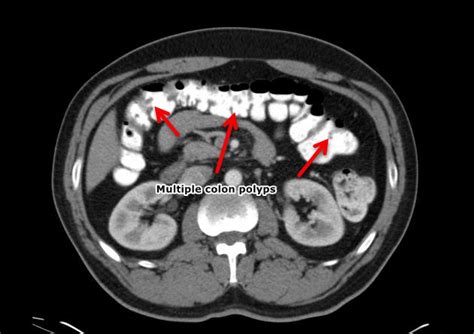

Polyps are small growths on the inner lining of the colon or rectum. They are usually benign (non-cancerous), but they can develop into cancer over time. There are several types of polyps, including:

- Adenomatous polyps: These are the most common type of polyp and have the potential to develop into cancer

- Hyperplastic polyps: These are small and usually harmless, but can sometimes develop into cancer

- Inflammatory polyps: These are caused by inflammation in the colon or rectum and are usually harmless